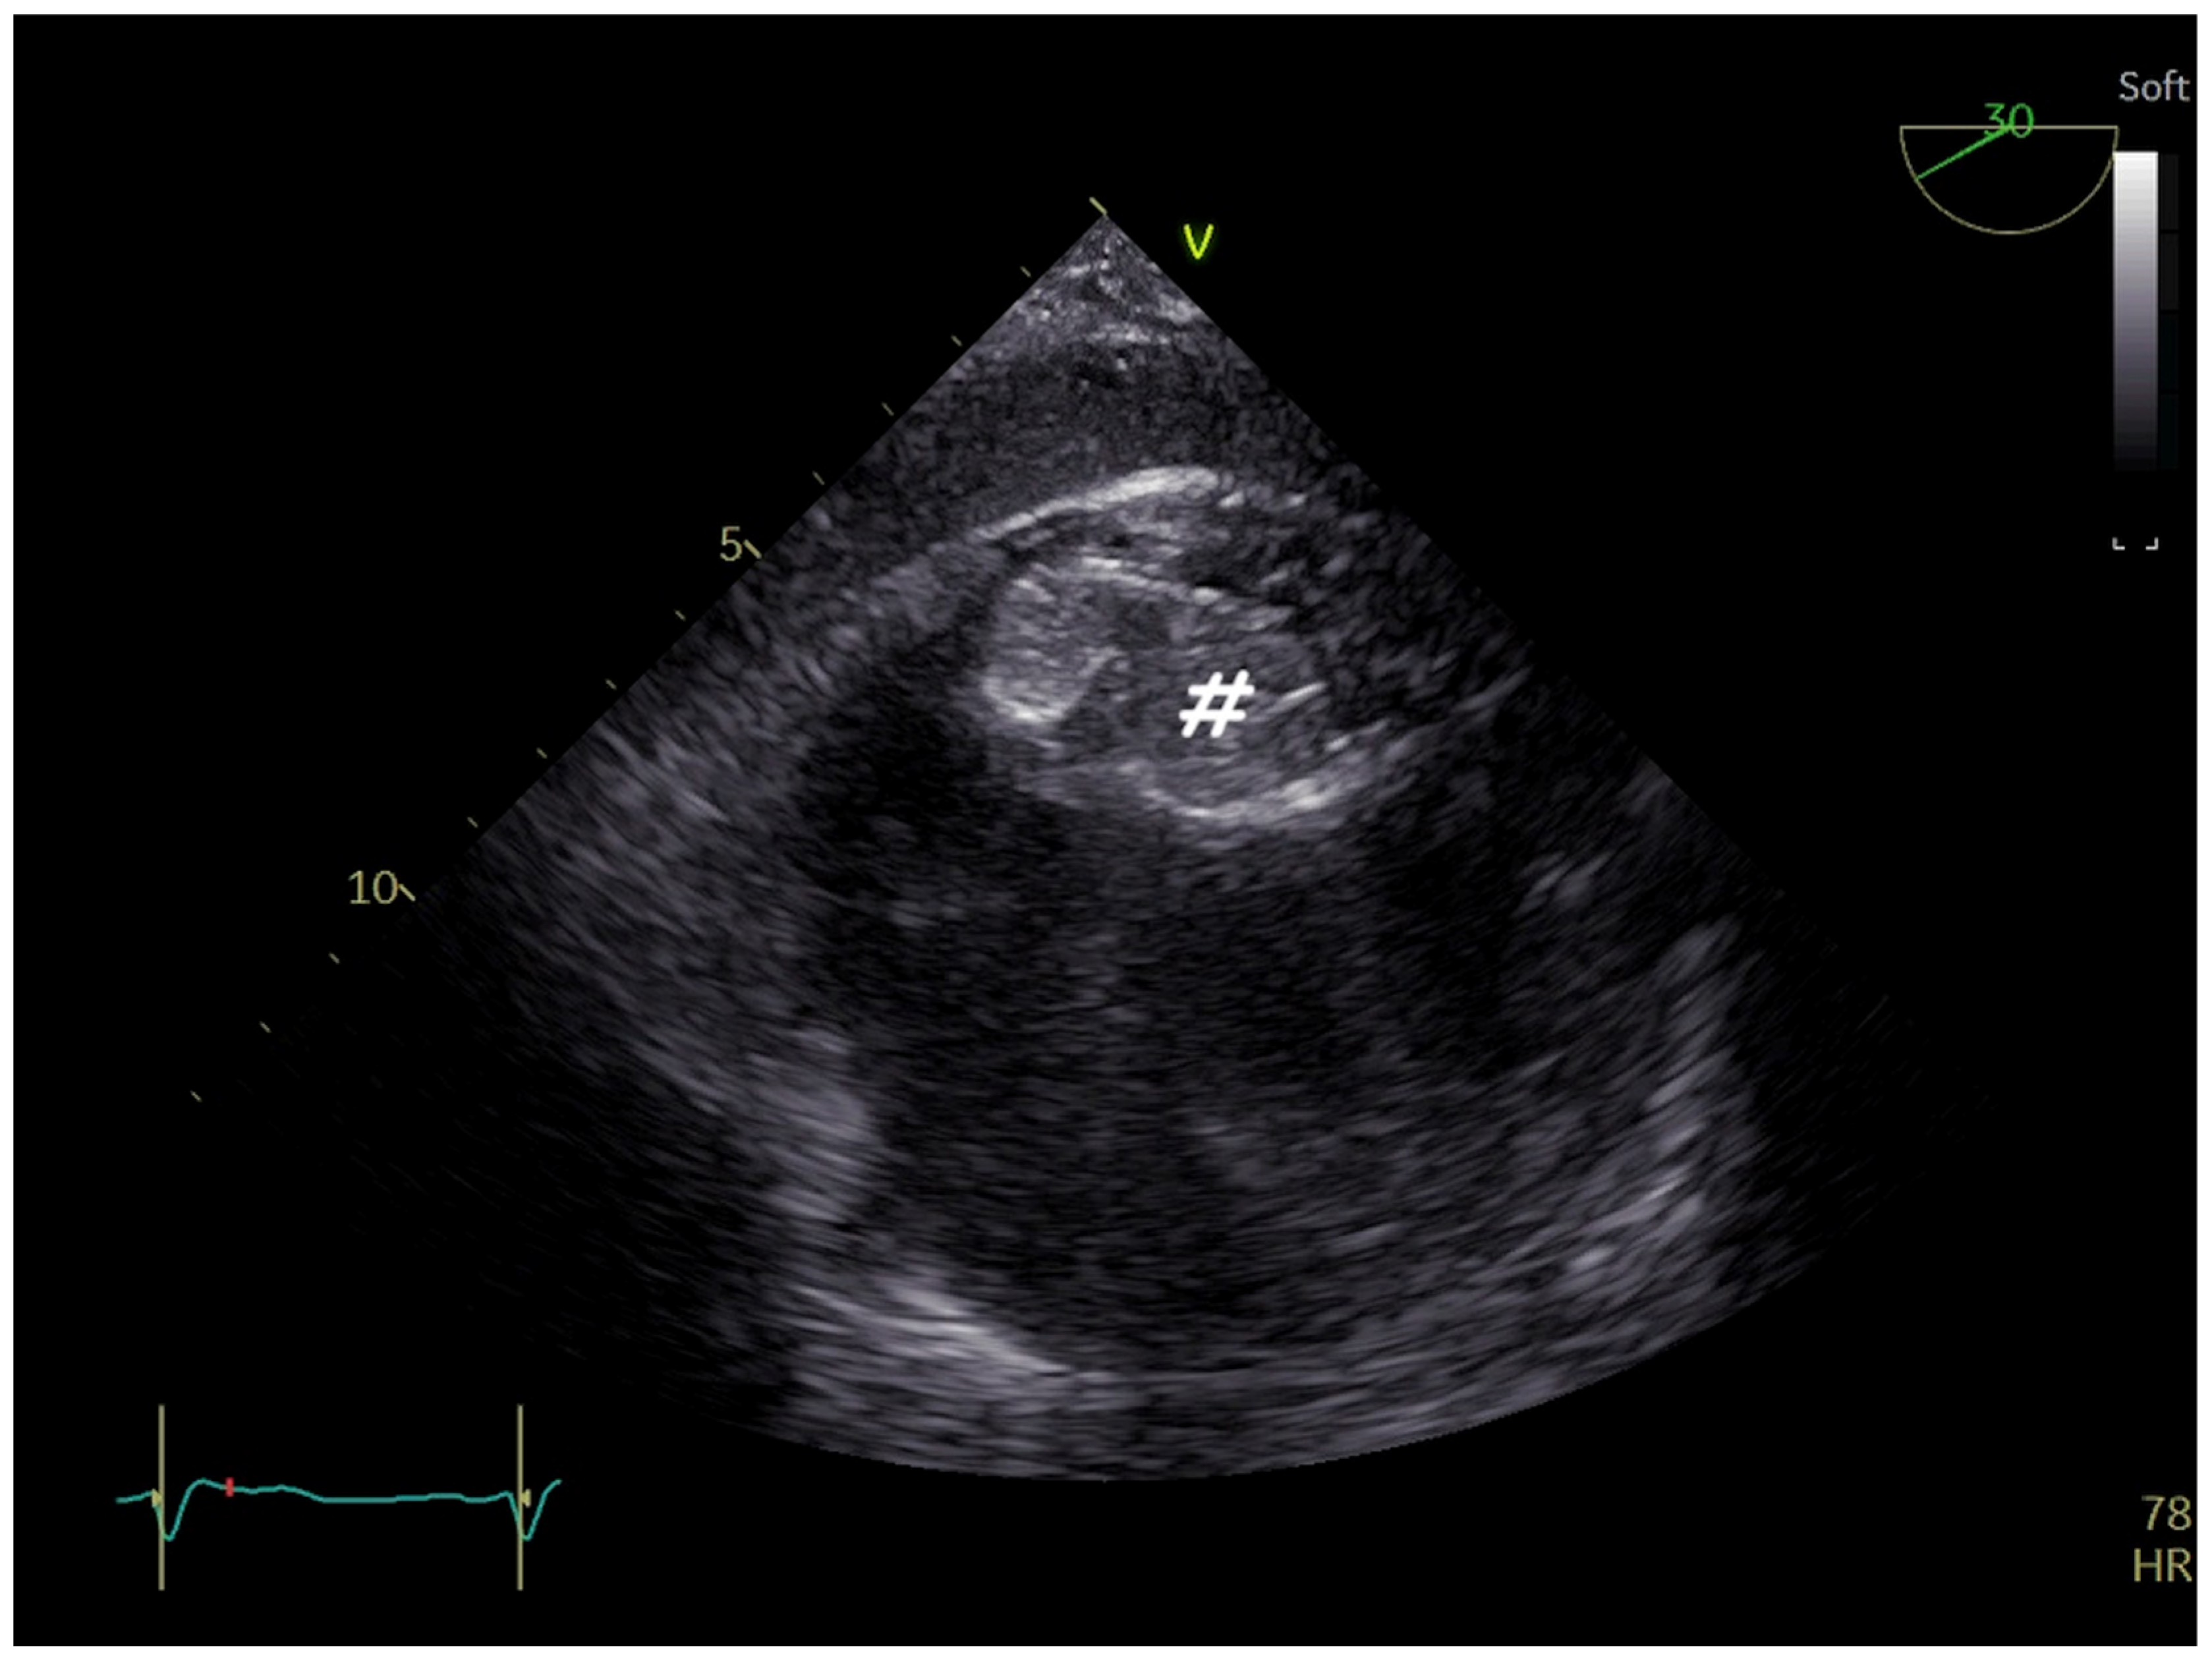

6. Ruptured Sinus of Valsalva Closure